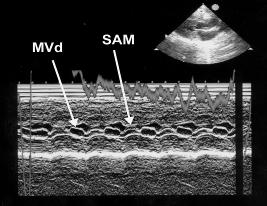

This image shows systolic anterior mitral valve motion (SAM) (arrows). The mitral valve is pulled up into the left ventricular outflow tract during systole. SAM can be created by a venturi effect as high flow velocity in a narrowed outflow tract drags the leaflet upwards. It may also be produced by abnormal alignment of the papillary muscles resulting in displacement of the mitral leaflet during systole. Regardless of the cause, its presence implies outflow obstruction. Below are more examples of SAM on m-mode and 2D images. |

Arrows show the systolic anterior mitral valve motion (SAM). Use the left ventricular wall motion to help you identify the systolic time period. VS = ventricular septum, MV = mitral valve, LVW = left ventricular wall, RV = right ventricle, LV = left ventricle, AO = aorta, LA = left atrium, MVd = mitral valve in diastole |